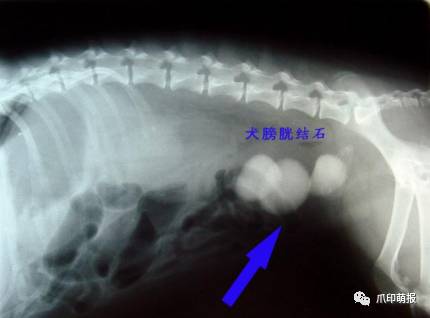

引起尿道阻塞的原因有感染、发炎、结石、肿瘤等原因,如果是部份阻塞,当膀胱内尿液的压力大于阻力时,尿液及会不自主的流出,引起尿*禁失**。

膀胱是储存尿液的位置,在膀胱发炎或结石的时候,因为膀胱壁的过度刺激,引起膀胱平滑肌的收缩,造成不定期的排尿,也可能是因为膀胱内壁有肿瘤的生长,引起尿液储存量降落,而引起排尿频率上升。

饲主需要仔细视察小狗排尿时的行为与时间,提供给兽医师完整的讯息,兽医师也会藉由理学检查、神经学检查、腹腔触诊、血液学检查、x光检查、膀胱造影术、尿液分析等方法,详细的评估出漏尿的原因。